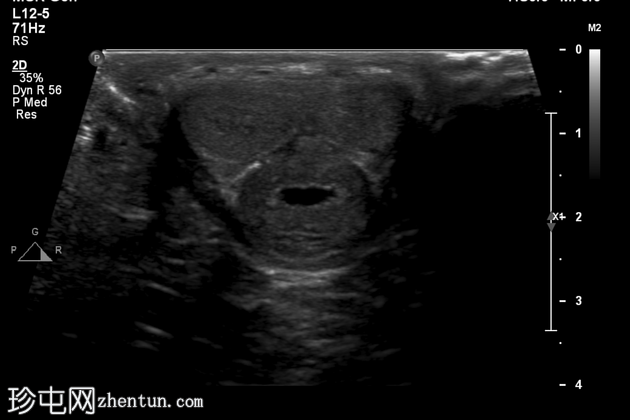

超声检查

阴茎远端可见异常环周增厚,龟头可见边界不清的低回声病灶。

远端尿道轻度扩张。

左侧腹股沟淋巴结异常,皮质增厚,淋巴门消失。